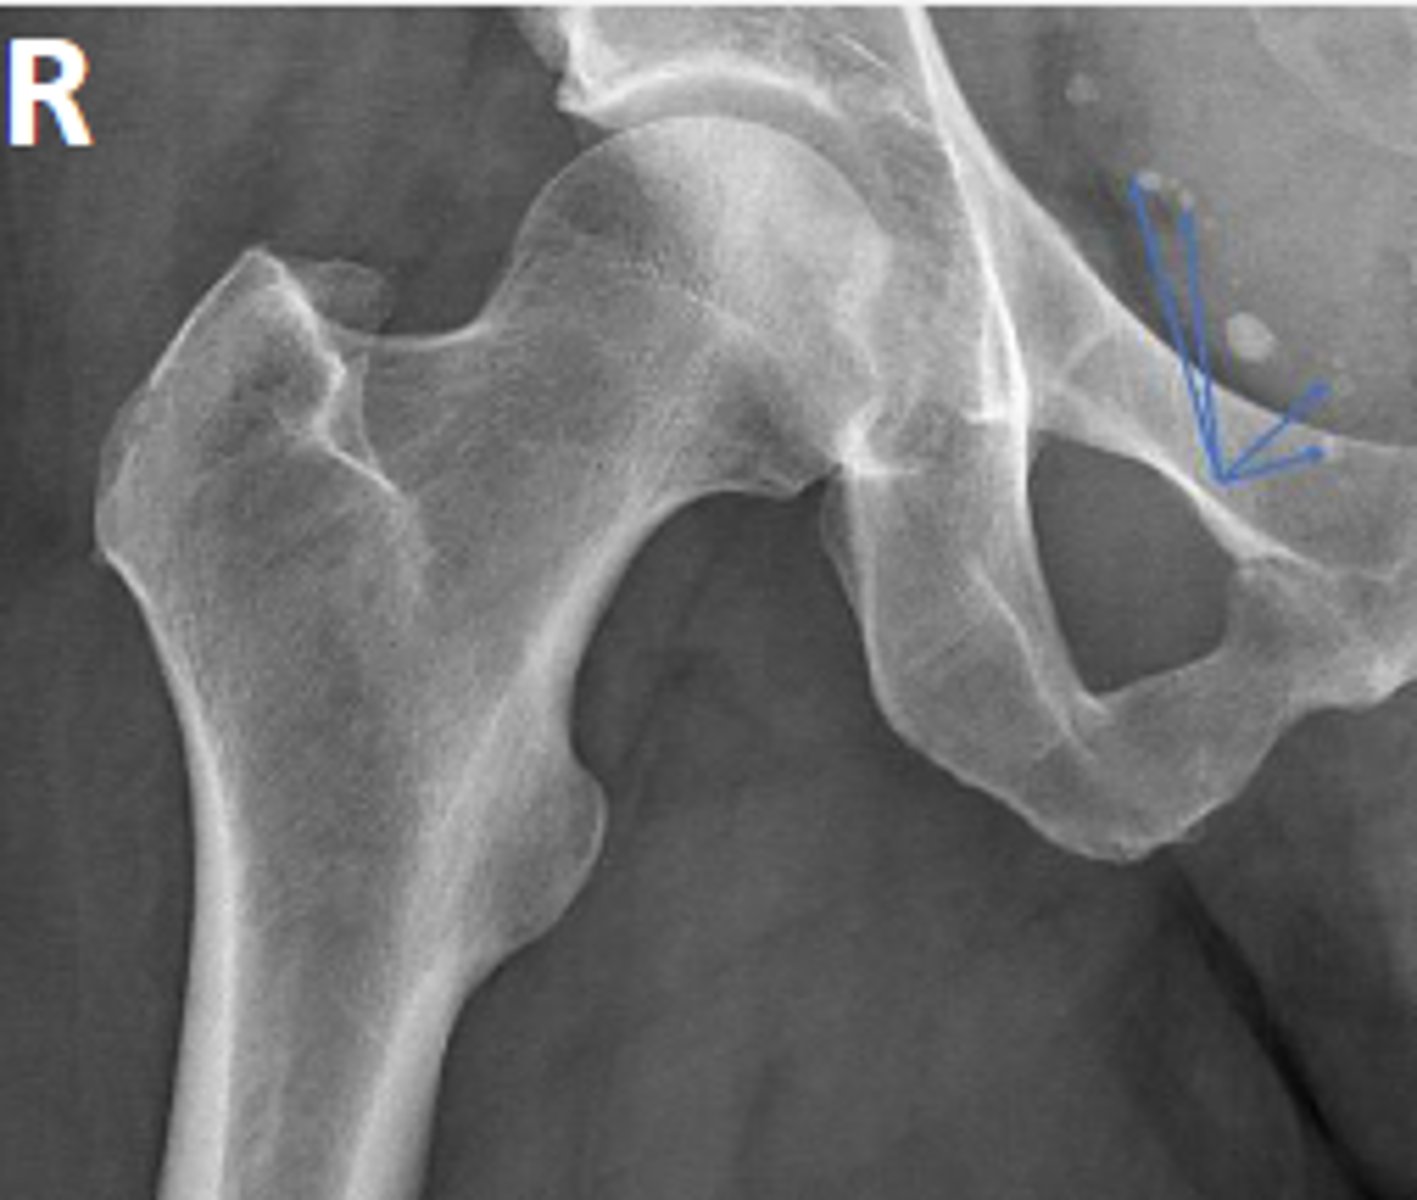

Phleboliths

What are the arrows pointing to?